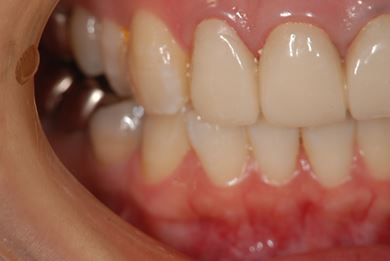

| 性別/年齢 | 女性 / 27歳 | ||||||||||||||||||||||||||||||||

| 主訴 | 審美歯科治療を希望。歯ならびもできるかぎりそろえたい。 | ||||||||||||||||||||||||||||||||

| 治療内容 | オールセラミック4本(オールセラミック用土台4本)、メタルボンドセラミック2本(メタルボンドセラミック用土台2本) | ||||||||||||||||||||||||||||||||

| 総治療費 | 867,825円 | ||||||||||||||||||||||||||||||||

| 治療期間 | 5ヶ月 |